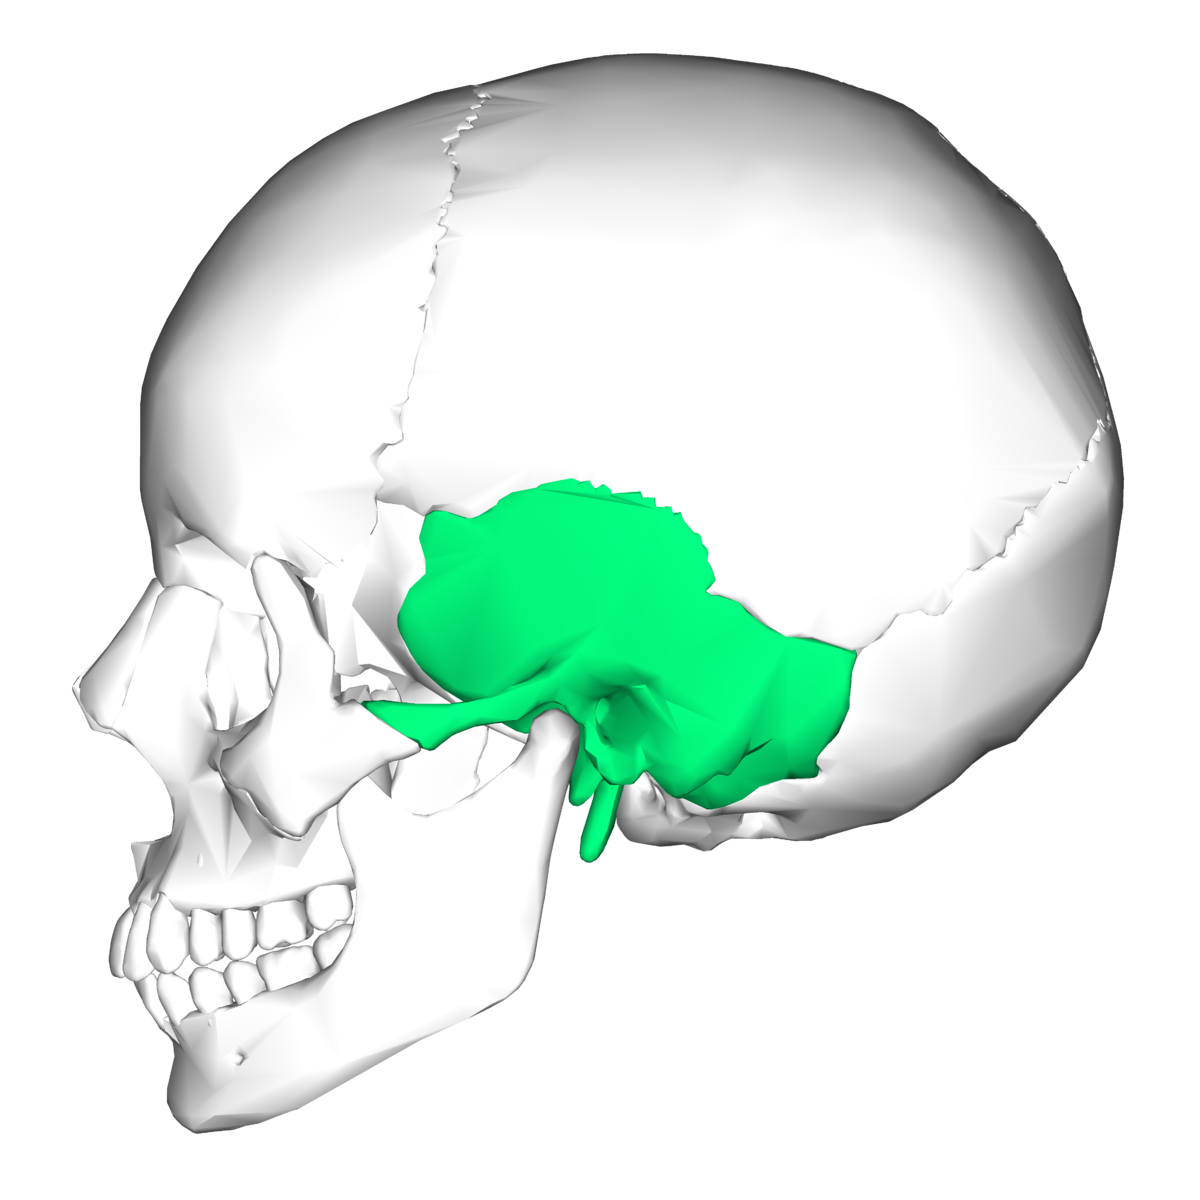

What bone is this?

Temporal bone

What are the important structures in the temporal bone you need to know about?

Show the location of the temporal bone and name the 3 main parts of the bone.